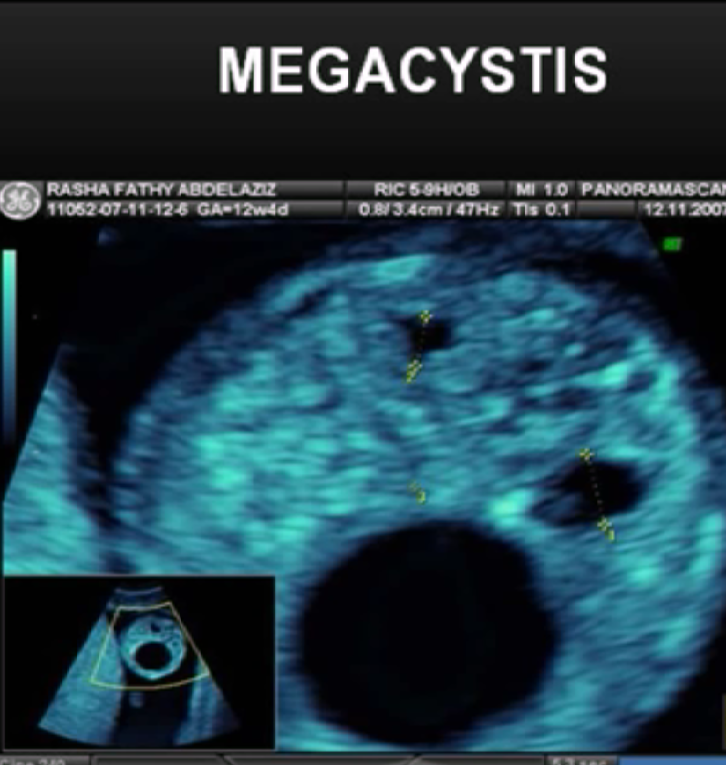

产科超声-胎儿早期评价